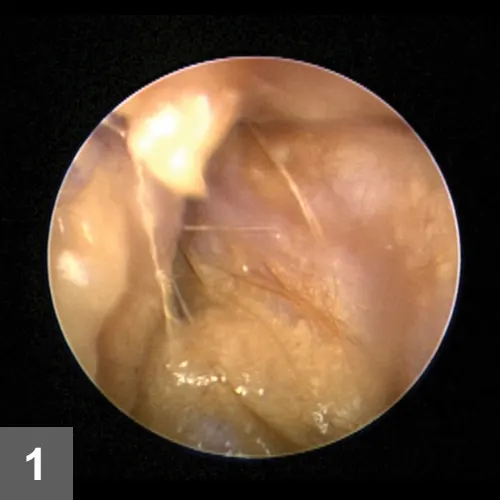

Figure 1. On presentation, stenosis of the horizontal canal with purulent exudate was noted during otoscopic examination in a 3-month-old shar-pei.

The ear canals were palpably firm and pliable, and pain was elicited during external manipulation. The pinnal–pedal reflex was negative. Otoscopic examination revealed bilateral moderate erythema and severe stenosis of the horizontal ear canals with purulent exudate (Figure 1).